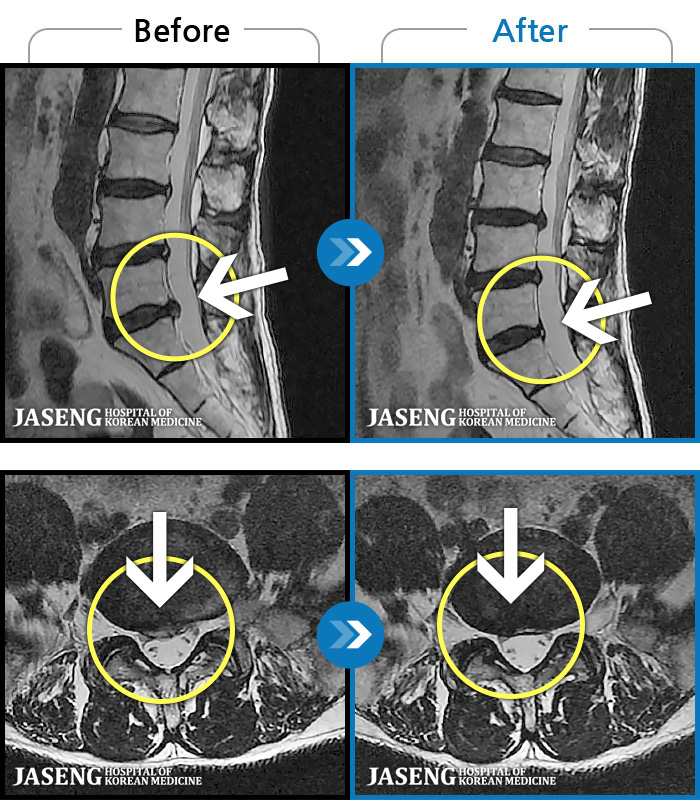

1,268 MRI ũ ʸ Ȯϼ.

ȯںп Ǹ ǿ ԿǾ, ο ġ ۿ Ƿ ġḦ Ͻñ ٶϴ.